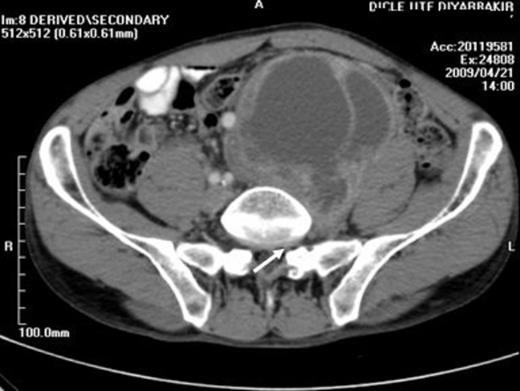

A 57-year-old man presented with a 3-month history of vague abdominal pain. There was no family history of RSs. The bowel and bladder habits were normal. On physical examination, there was a large, firm, non-tender palpable abdominal mass behind the umbilicus. There was no palpable lymphadenopathy. All vital signs, the chest X-ray, haemogram, biochemical analysis and tumor markers were normal. Computed tomography (CT) confirmed a 9×9x12 cm large, heterogeneous, multilocular, cystic mass with a thick wall and irregular septum in the left retroperitoneal area (Figure 1).

A CT image showing a heterogeneous, multilocular, cystic mass which is localized to the anteromedial aspect of the psoas muscle begining from the left L5 - S1 intervertebral foramina

It was localised to the anteromedial aspect of the psoas muscle extending from L4 to S1. The left common iliac, external and internal iliac arteries were displaced medially and both the external and internal iliac veins were dilated. The common iliac vein was not separated from the mass. (Figure 2)